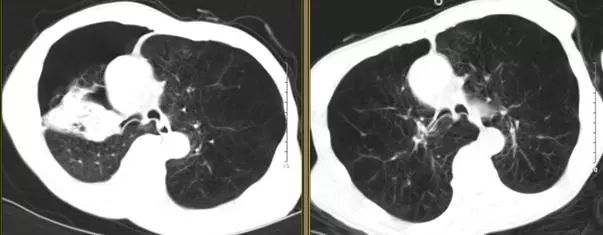

高分辨胸部CT提示:肺气肿以双肺上叶为著,右肺上叶肺大疱,中叶呈外压性条索状,右侧斜裂完整。

图7 术前2天(右)与术后5天(左)胸部CT对比